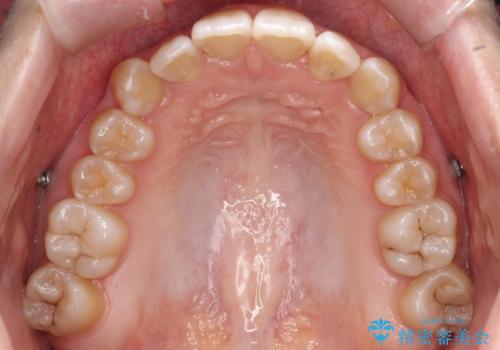

- 前歯のデコボコ(叢生)と、前歯が上下逆の咬み合わせ(反対咬合)を主訴にご来院されました。精密検査の結果、歯列全体のスペースが不足していることが判明。患者様のご希望に合わせ、透明で目立ちにくい**インビザライン(マウスピース矯正)**による治療計画を立案しました。歯を抜かずに、歯列全体を奥(遠心)へ移動させることで、歯が並ぶスペースを確保し、叢生と反対咬合を同時に改善することを目指します。

今回の矯正治療では、透明なマウスピース型の装置インビザラインを使用しました。この装置は目立たず、取り外しが可能なため、食事や歯磨きも普段通り行えます。治療は、緻密な治療計画に基づき、段階的に作製されたマウスピースを交換していくことで、遠心移動という方法で奥歯から徐々に歯列全体を後方へ動かしました。これにより、不足していたスペースを確保し、前歯のデコボコを解消。同時に、上下の歯の前後的な関係を改善することで、反対咬合も正常な咬み合わせへと導きました。見た目も機能も改善し、自然で美しい笑顔を獲得していただけました。